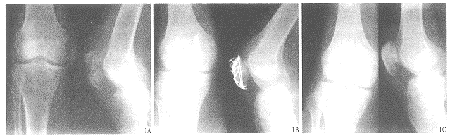

三角形张力带内固定治疗髌骨粉碎性骨折

摘要 目的 观察三角形张力带内固定治疗髌骨粉碎性骨折的疗效。方法 对20例髌骨粉碎性骨折患者进行三角形张力带内固定治疗。结果 20例均达骨性愈合,6~13个月后去除内固定物。膝关节功能按胥少汀评分法优13例,良7例。结论 三角形张力带内固定治疗髌骨粉碎性骨折具有固定牢固、可早期行功能锻炼等优点。